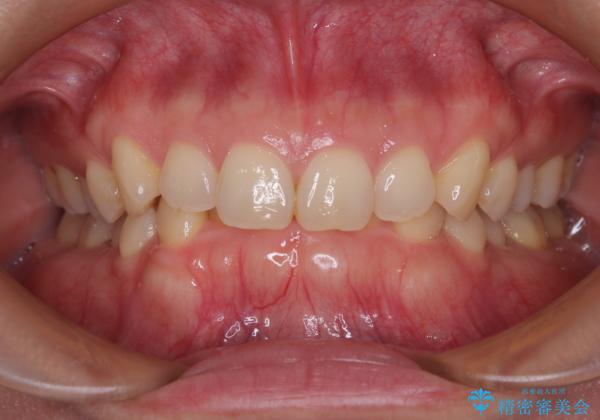

- 下顎前歯が完全に隠れてしまっていることを気にして来院された患者様です。

下顎の臼歯が手前に傾斜していることで咬み合わせが深くなってしまい、下顎前歯が見えないほどに上顎前歯が覆い被さっている状態でした。

下顎臼歯を起き上がらせるためにユーティリティーアーチを使用し、一気に深い咬み合わせを改善することができました。